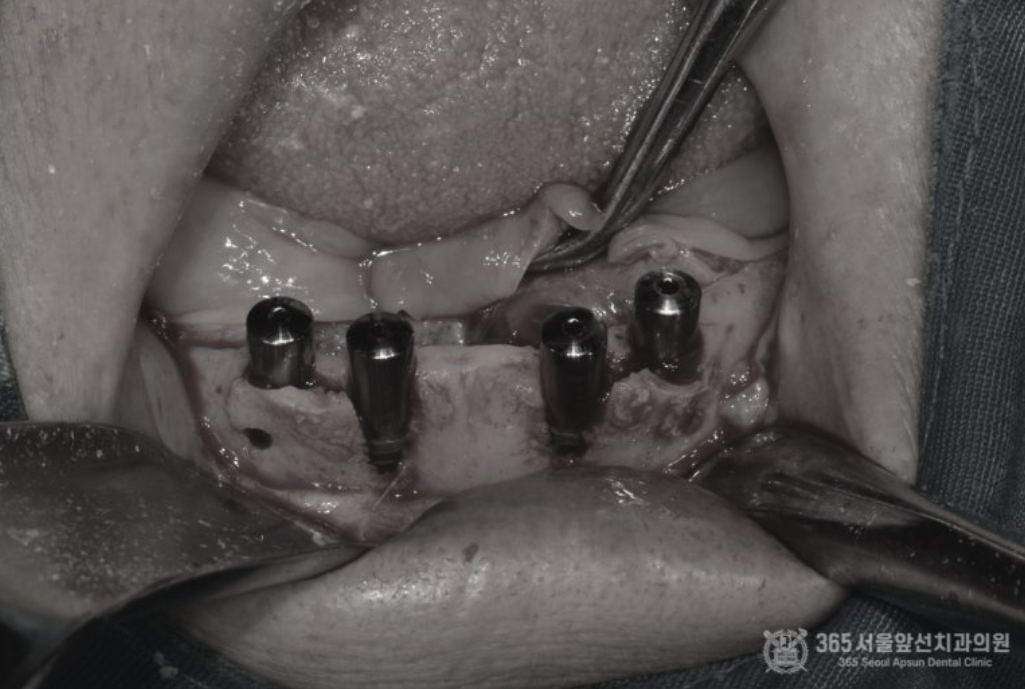

골다공증이 심해서 임플란트가 불가능하다는 이야기를 들었어요. 임플란트가 가능할까요? 상기 환자분은 골다공증으로 치료를 받고 계신 환자분이십니다. 골다공증제를 복용하고 계시거나, 골다공증 치료제 주사를 맞고 계실 경우 임플란트 치료시 고려되어야 하는 것은 널리 알려진 사실입니다. 결론부터 말씀드리자면 골다공증 치료를 받고 계시더라도 주치의와 상의해서 스케줄을 조율한다면 대부분 큰 무리 없이 임플란트 치료를 받으실 수 있습니다. 촬영일시 : 2024.07.05. 처음 내원 당시 엑스레이 사진입니다. 한눈에 보기에도 뼈가 거의 없어서 임플란트 치료가 쉽지 않으신 환자분입니다. 또한 엑스레이에서 보다시피 뼈의 밀도가 낮아서 뼈가 어둡게 보입니다. 골다공증 병력을 가진 환자분들에서 종종 나타나는 국소골다공성골수결손(Focal osteoporotic bone marrow defect) 양상을 보이셨던 환자분입니다. 촬영일시 : 2024.07.05. 임플란트 식립시 뼈의 모습입니다. 텅 빈 공간에 임플란트가 덩그러니 있는 듯한 모습이지만, 해당 공간은 임플란트를 식립하기 위해 뼈에 구멍을 낸것이 아니라 골수 결손으로 인해 원래부터 빈 공간이었던 부분입니다. 그 만큼 뼈의 상태가 매우 좋지 않았다는 것을 알 수 있습니다. 촬영일시 : 2024.07.05. 아래 앞니 부위도 뼈가 매우 얇아서 임플란트 식립시 뼈를 쪼개서 식립(ridge splitting)해야 할 정도로 매우 상태가 좋지 않았습니다. 촬영일시 : 2024.07.11. 수술이 잘 마무리된 후 엑스레이 사진 및 구강 내 사진입니다. 촬영일시 : 2024.11.11. 4개월 후 최종 보철물을 제작했습니다. 위턱은 전체임플란트로 치료를 마무리 지었고, 아래턱은 임플란트 브릿지와 틀니를 조합하여 잘 마무리해 드렸습니다~ ^^ 촬영일시 : 2024.07.05. / 2024.11.11. 구강 내 전후 비교사진입니다. 완전히 달라진 전후 모습을 비교할 수 있겠습니다. 오늘은 골다공증으로 인해 국소 골다공성 골수결손(focal osteoporotic bone marrow defect)이 발생된 환자분의 전체 임플란트 치료 증례를 소개해드렸습니다. 수 없이 많은 전체 임플란트 환자분들을 치료 하다보면 전신질환으로 인해 치료가 쉽지 않은 경우가 종종 있습니다. 하지만 질환을 잘 이해하고 있는 치과의사와 함께 한다면 치료를 잘 마무리 하실 수 있으니 걱정안하셔도 되겠습니다. 365서울앞선치과 대표원장 강동우였습니다. 감사합니다 ! [ 치료기간: 2024년 7월5일 ~2024년 11월 11일 ] ※ 365서울앞선치과의원의 모든 컬럼은 각 진료과 의료진이 직접 작성합니다. 365서울앞선치과의원 임상 케이스 게시물은 환자분께 의학적으로 정확하고 상세한 정보를 드리기 위해 각 진료과 의료진이 직접 작성하며, 모든 증례 사진은 본원 의료진이 직접 시술한 증례를 촬영한 것으로, 의료법 제23조, 제56조에 의거하며 환자분의 동의를 얻어 포스팅에 사용하였습니다. 또한 해당 케이스는 본 환자분의 치료 결과이며, 환자 상태에 따라 치료의 결과는 달라질 수 있습니다. |